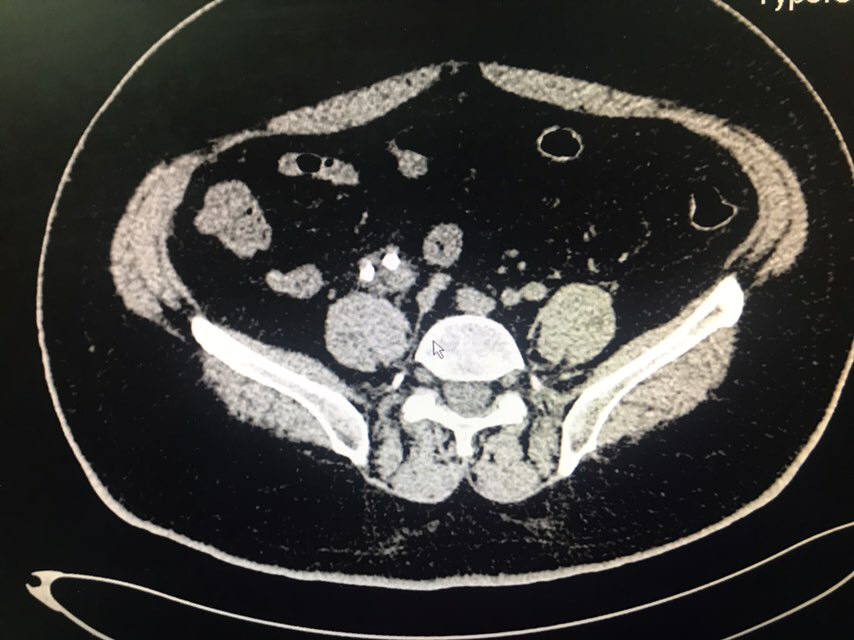

查体:无特殊。辅助检查:全腹CT(我院2018-8-6):右肾盂、肾盏及右输尿管上段明显扩张、积水;右侧输尿管置管。左肾盏区点状结石;双肾囊肿可能。膀胱充盈,壁稍增厚、毛糙,合并炎症可能,胆囊结石。脂肪肝;肝右叶小钙化灶。

从患者CT片子上看,患者右侧输尿管下段狭窄,输尿管支架管返折,因膀胱镜下未能成功取出,故行右侧输尿管探查术。手术顺利,术后给予曲克芦丁脑蛋白水解物注射液5ml治疗,患者术后恢复良好。